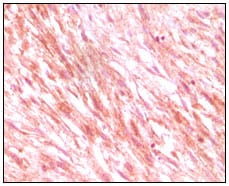

Mouse Monoclonal Antibody to PR

| IHC | 1/200 - 1/1000 |